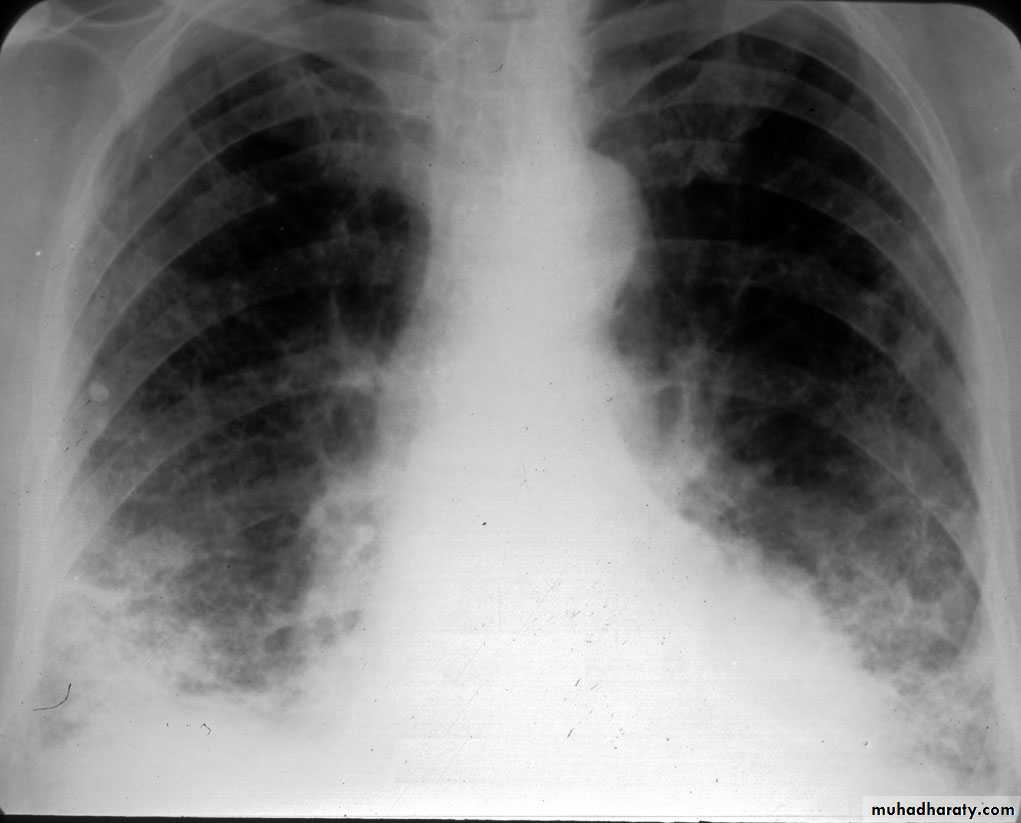

Radiology

Chest X-ray: typically small lung volumes with reticulonodular shadowing

HRCT: reticulonodular shadowing in early stage and honeycomb cysts and traction bronchiectasis in advance stage.

Abnormal chest X-ray at presentation with lower zone bi-basal reticular and reticulonodular opacities. 'honeycomb' appearance in advanced disease.

HRCT may be diagnostic, demonstrating a patchy, predominantly peripheral, subpleural and basal reticular pattern with subpleural cysts (honeycombing).